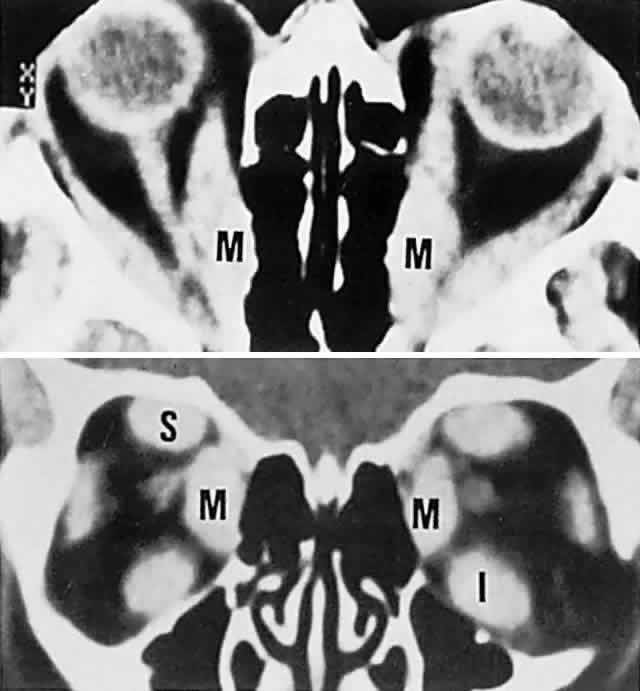

Graves' disease is the overwhelming single most common cause of single or multiple extraocular muscle thickening (Fig. 18; see also Volume 2, Chapter 12, Figs. 28 and 30); inflammatory myositis is considerably less frequent, and muscle metastases are quite rare. Passive congestive myopathy also accompanies arteriovenous shunts and lesions of the superior orbital fissure and cavernous sinus, where orbital venous return is obstructed. The capacity of CT to detect minor to moderate changes in muscle diameter is perhaps limited,70 and standardized A-scan ultrasonography seems more sensitive and practical.71

Fig. 18. CT scan in Graves' disease. Top. Axial section shows massively enlarged horizontal recti (M, medial) with packed apex. Bottom. Coronal section demonstrates enlarged medial (M), superior (S), and inferior (I) recti.